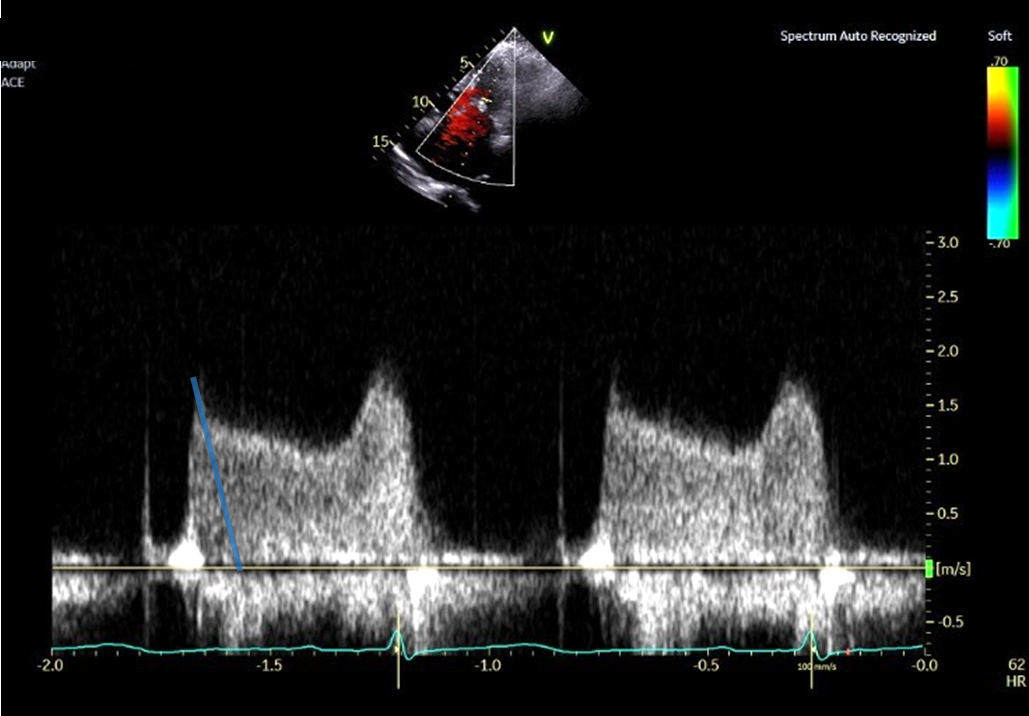

PHT法 拡張早期の急峻な部分から計測した場合 (No15_1)

③ PHT法で弁口面積を求める際は、拡張早期の急峻な部分を避けて計測する